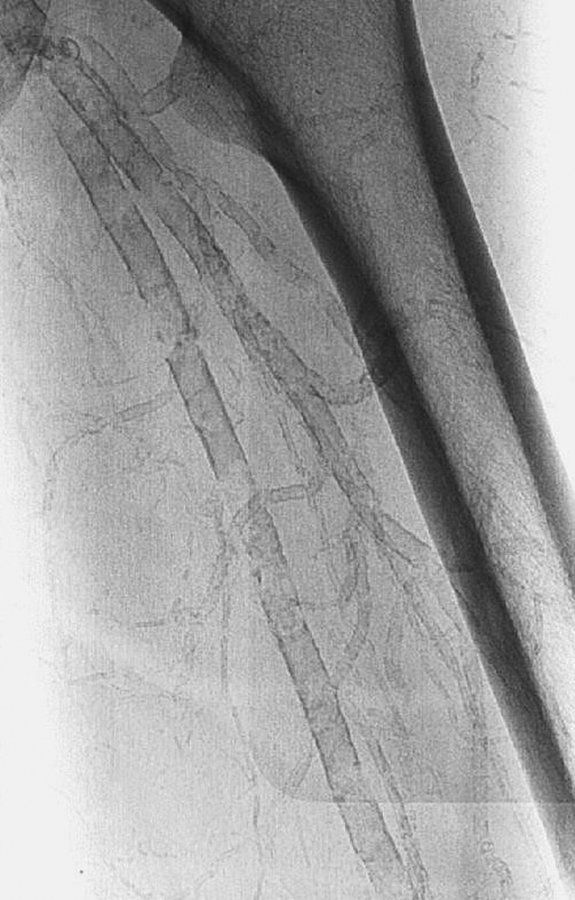

Um den Knöchel-Arm-Index zu berechnen, erfolgt die Doppler-Druckmessung der Aa. brachialis (1), dorsalis pedis (2) und tibialis posterior (3). Gebildet wird jeweils der Quotient aus Fuß- und Armarteriendruck. Um den Knöchel-Arm-Index zu berechnen, erfolgt die Doppler-Druckmessung der Aa. brachialis (1), dorsalis pedis (2) und tibialis posterior (3). Gebildet wird jeweils der Quotient aus Fuß- und Armarteriendruck. © Mediengruppe Oberfranken – Fachverlage GmbH & Co. KG, Kulmbach